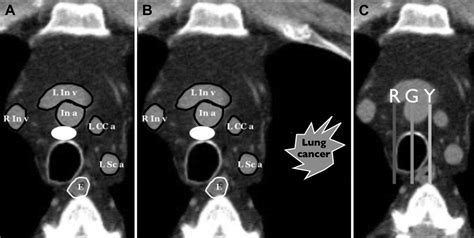

Characteristics Analyzed by Radiologists

When a radiologist reviews a Node In Lung Ct Scan, they look for specific physical characteristics to determine the likelihood of the nodule being benign or requiring further investigation. By evaluating the size, shape, and internal density of the spot, doctors can categorize the risk level. The following table illustrates how different features are generally interpreted during a clinical assessment:

• PET Scans or Biopsies: If a nodule appears suspicious or grows during the observation period, the physician may order a PET scan to check for metabolic activity or a biopsy to extract a small sample of tissue for laboratory testing.